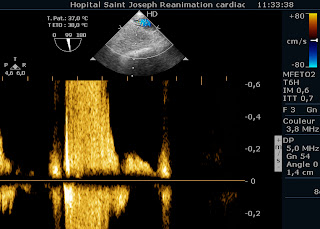

Mais chacun sait qu’on écoute, aux portes (ouah, la blague du siècle! heureusement que vous êtes tous en vacances…), et Madame à un souffle à l’auscultation. Un PDS. (Putain De Souffle). Alors, on redécouvre l’insuffisance mitrale sur prolapsus complexe, avec un jet par prolapsus commissural antérieur, et un prolapsus du feuillet antérieur. En ETO, le reflux systolique est franc dans la veine pulmonaire inférieure droite.

Mais le flux dans les autres veines pulmonaires est normal.